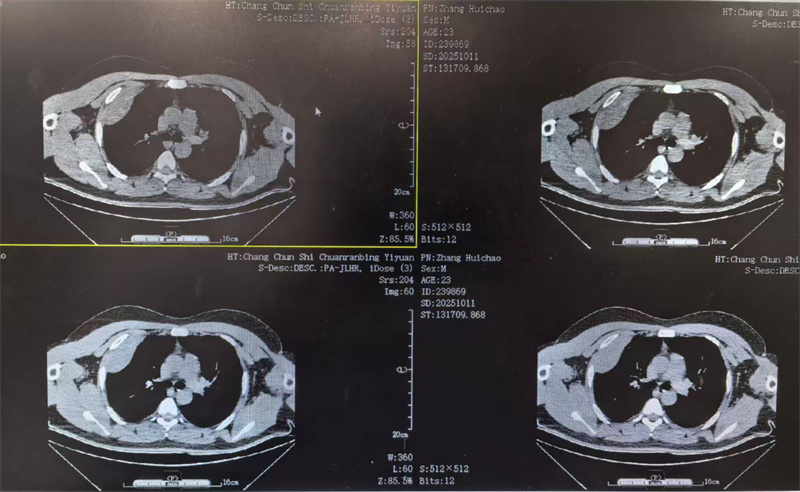

四个月前,23岁的小雨(化名)因胸闷前往医院就诊,CT检查结果显示右侧胸腔靠上位置出现包裹性脓胸,并进行穿刺检查,最终确诊为结核性包裹性脓胸,这个消息让小雨和家人陷入了深深的焦虑之中。

看着日益憔悴的小雨,医生建议手术治疗。术前,田子刚主任和宋巍峰医生在全面评估了小雨各项指标后,确定符合手术标准,便与麻醉科以及护理团队紧密配合,为小雨实施胸腔镜下胸膜剥脱术。